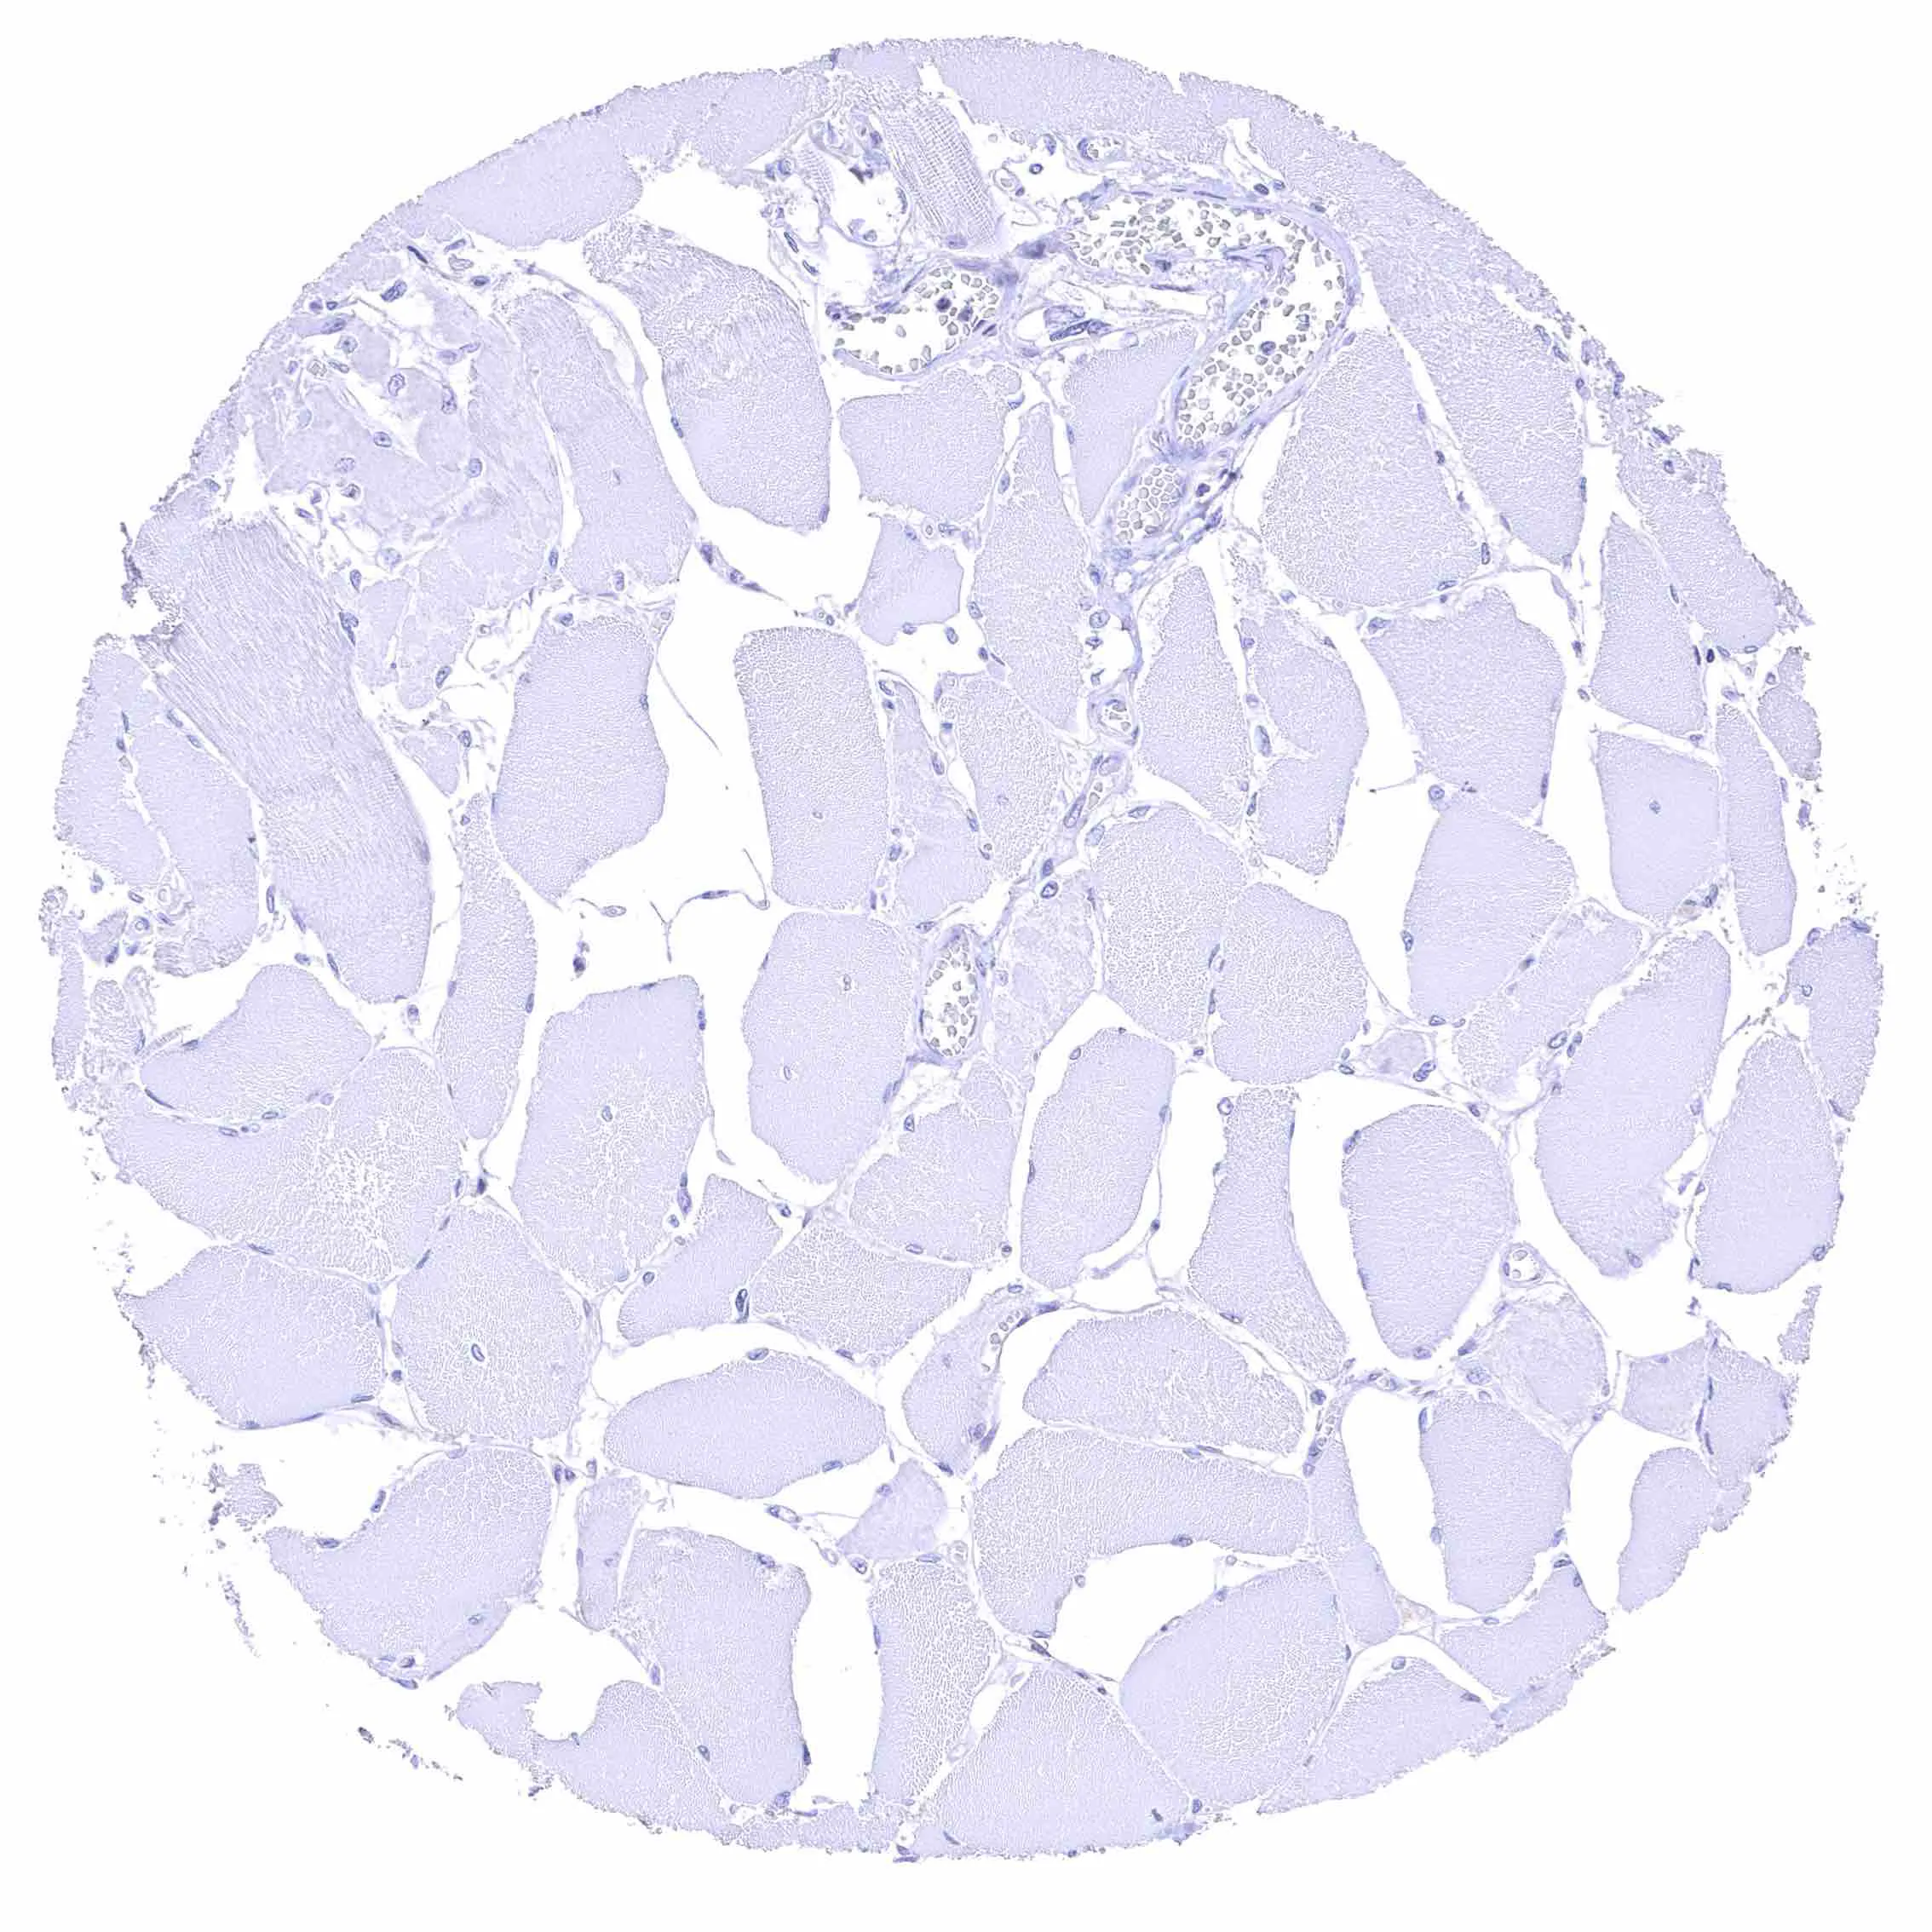

Skeletal muscle